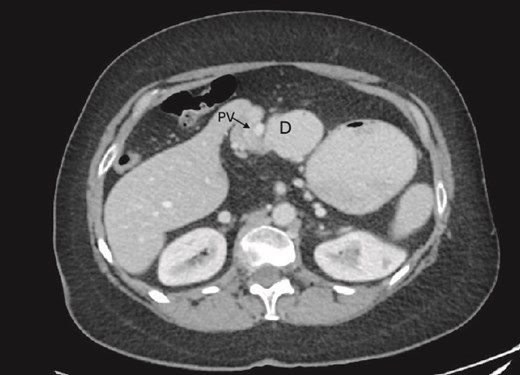

On examination, the abdomen was soft but mildly distended. Bowel sounds were heard, and the epigastrium was mildly tender. Standard bloodwork was normal. Review of an abdominal computerized tomography (CT) scan from 4 years prior showed congenital malrotation of the bowel, with the small bowel to the left of the midline and colon entirely to the right (Fig. 1). There was partial agenesis of the dorsal pancreas (Fig. 2), azygous continuation of the inferior vena cava (IVC), a retroaortic and retrocrural left renal vein, and an unremarkable spleen alongside some splenules. The PV traversed anterior to the first part of the duodenum (Fig. 3). There was relative narrowing of the distal stomach and the duodenum was nondilated.

Terminal ileum (*) seen entering cecum with completely right-sided colon and left-sided small bowel visible. PDPV also seen (^) causing partial duodenal obstruction.

Preduodenal PV seen crossing the duodenum (D) causing partial obstruction.